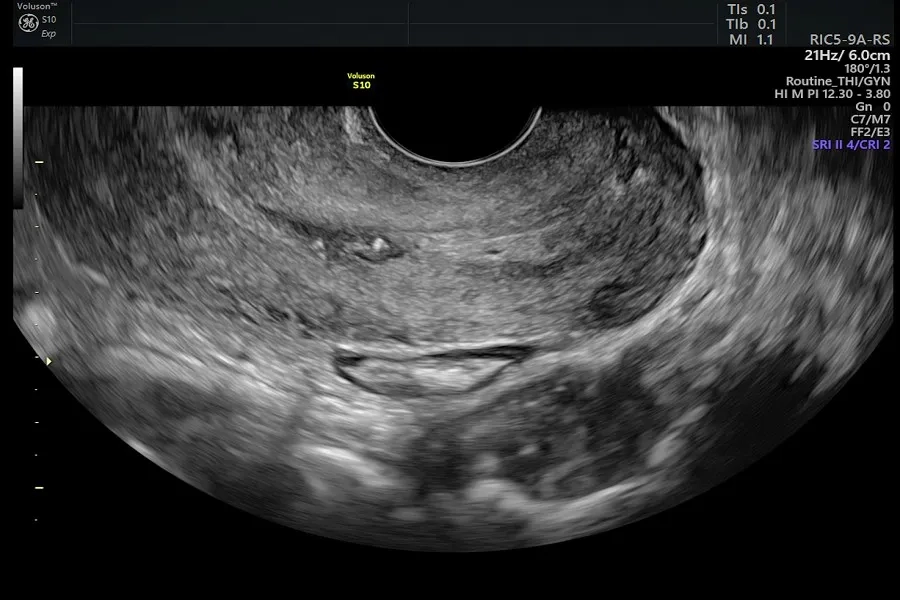

- Siêu âm tuyến vú: Dùng sóng âm tạo hình ảnh cấu trúc vú, giúp phân biệt khối rắn và nang dịch. Cũng được dùng để định vị vùng nghi ngờ trước khi sinh thiết hoặc kiểm tra di căn gan khi bệnh tiến triển.

- Cộng hưởng từ (MRI) tuyến vú: Dùng từ trường và sóng radio để tái tạo hình ảnh chi tiết. Thường chỉ định khi nhũ ảnh hoặc siêu âm không rõ ràng, hoặc để kiểm tra vú còn lại. Trước khi chụp, có thể tiêm thuốc cản quang để hình ảnh rõ hơn.